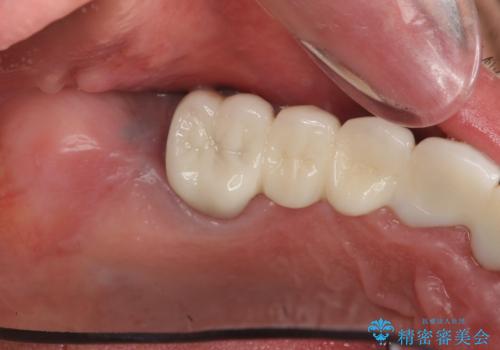

長らく気になっていた歯ぐきの疼くような感じや、咬合機能が改善され、満足いただくことができました。